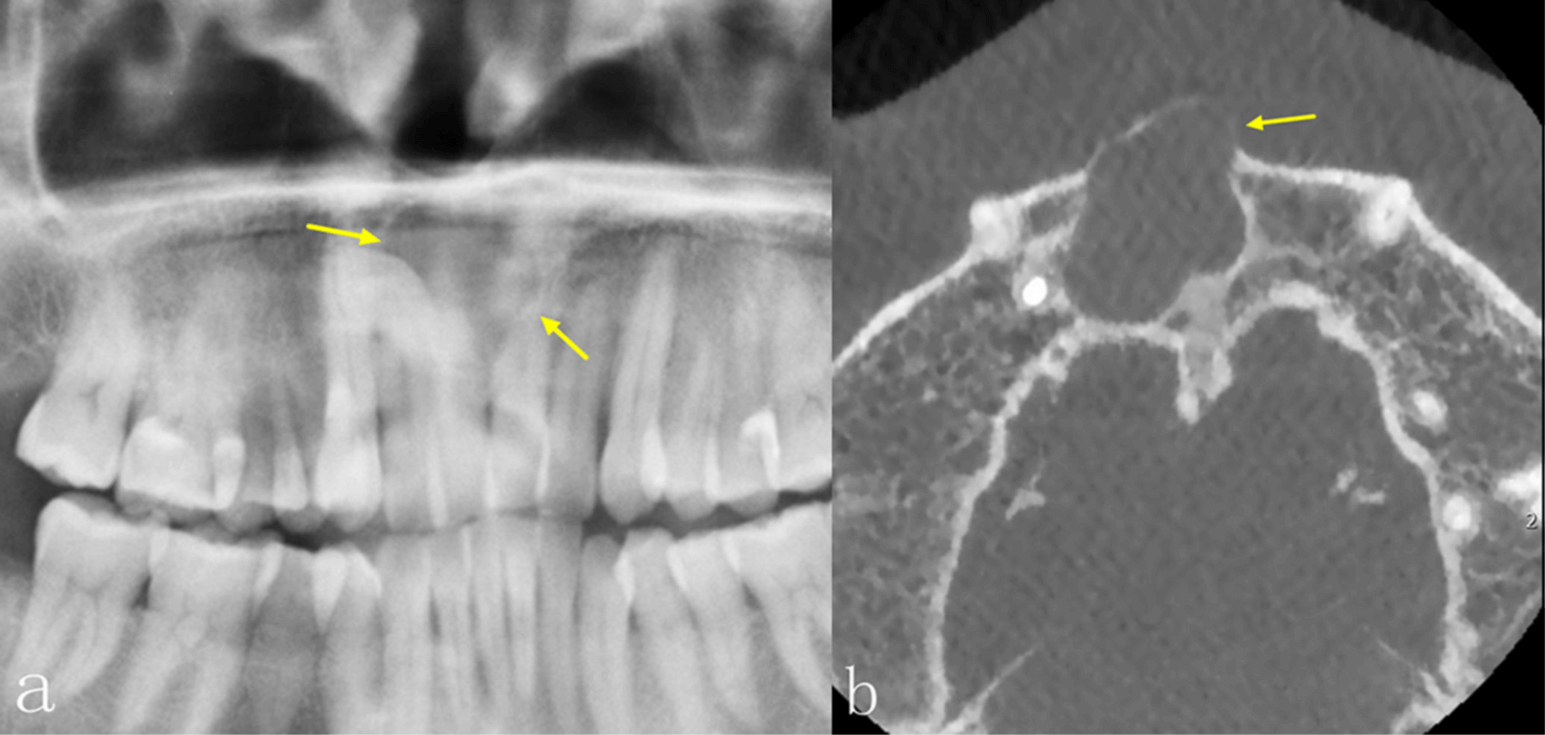

No obstante, la TCCB también tiene sus desventajas. Por ejemplo, la TCCB es propensa a diversos artefactos, especialmente artefactos metálicos y de movimiento, que pueden tener un efecto perjudicial sobre la calidad de la imagen. En comparación con la tomografía computarizada espiral (tomografía medica), su resolución de contraste es menor y los tejidos blandos se visualizan con menor calidad. La dosis de radiación y el coste son también factores importantes que deben tenerse en cuenta a la hora de tomar decisiones clínicas. La dosis depende principalmente del tipo de equipo y de los ajustes de exposición, incluyendo el campo de visión, el tiempo de exposición, la corriente del tubo (mA) y la energía/potencial (kV).6 En comparación con la PAN, la dosis efectiva de radiación de la TCCB suele ser significativamente mayor, lo que debe tenerse en cuenta cuando se requiere la obtención de imágenes. Las diferencias significativas en el aspecto radiológico de las lesiones intraóseas entre la PAN y la TCCB se encuentran en la integridad de los bordes corticales, la expansión de los límites anatómicos circundantes, el adelgazamiento cortical, la destrucción cortical y la reabsorción radicular, especialmente en las regiones anteriores de ambos maxilares y en el maxilar superior. La TCCB también mejora la precisión diagnóstica, especialmente en las lesiones del maxilar superior.

La TCCB proporciona información más completa y detallada, lo que resulta útil para realizar el diagnóstico. Aunque la precisión diagnóstica estaba estrechamente relacionada con la experiencia de los médicos, la discrepancia entre los dos estudios se atribuye muy probablemente al mayor tamaño de la muestra de nuestro estudio. La TCCB fue precisa a la hora de mostrar las características de las lesiones, como la ubicación, la localización, la densidad interna, la expansión y su efecto sobre las estructuras circundantes, lo cual es de ayuda a los odontólogos a realizar un diagnóstico más preciso.